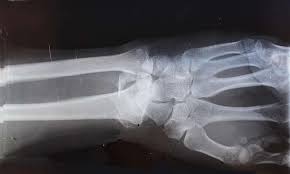

피로 골절이 자주 생기는 부위

피로 골절은 반복적으로 체중이 실리는 부위에서 흔히 발생합니다. 특히 아래 부위는 비교적 자주 언급됩니다.

• 발등과 발바닥 앞쪽